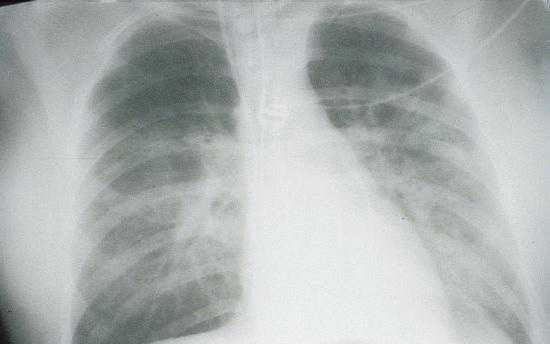

Radiologic Findings

HPS has a characteristic radiological evolution, beginning with minimal changes of interstitial pulmonary edema, progressing to alveolar edema with severe bilateral involvement. Pleural effusions are common and are often large enough to be evident radiographically. Heart size is usually normal. Cardiac silhouette size on chest radiographs is usually normal.

Approximately one-third of patients show evidence of pulmonary edema in the initial radiograph. Forty-eight hours after the initial radiograph, virtually all patients demonstrate interstitial edema and two-thirds have developed extensive bibasilar or perihilar airspace disease.

The lack of peripheral distribution of the initial airspace disease, the prominence of interstitial edema and the presence of pleural effusions early in the disease process help distinguish HPS from ARDS. There is, however, overlap in the radiographic appearance of the two diseases. Atypical pneumonias such as that caused by mycoplasm pneumonia can produce radiographic findings similar to early HPS, although the clinical illness tends to be much less severe.